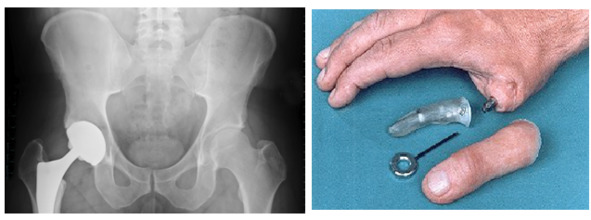

Виды имплантатов

История дентальных имплантатов

Предыстория создания дентальных имплантатов

Дентальные имплантаты 20 века